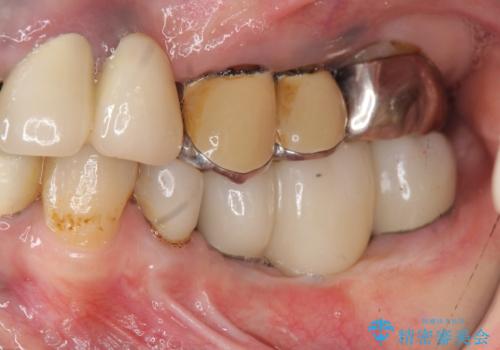

- 左下に長年使用した入れ歯が合わず、よりしっかりと噛みたいという希望で来院されました。

入れ歯をはずししっかりと噛む手段としてインプラント治療を進めていきます。

- 90万円(ストローマンインプラント×2・チタンカスタムアバットメント×2・ジルコニアクラウン×3)費用は治療当時の料金となります

インプラントを用いることで、たくさん失ってしまった奥歯を入れ歯よりもしっかりと噛む状態へと回復することができます。